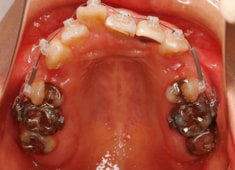

治療開始から1年8ヶ月後